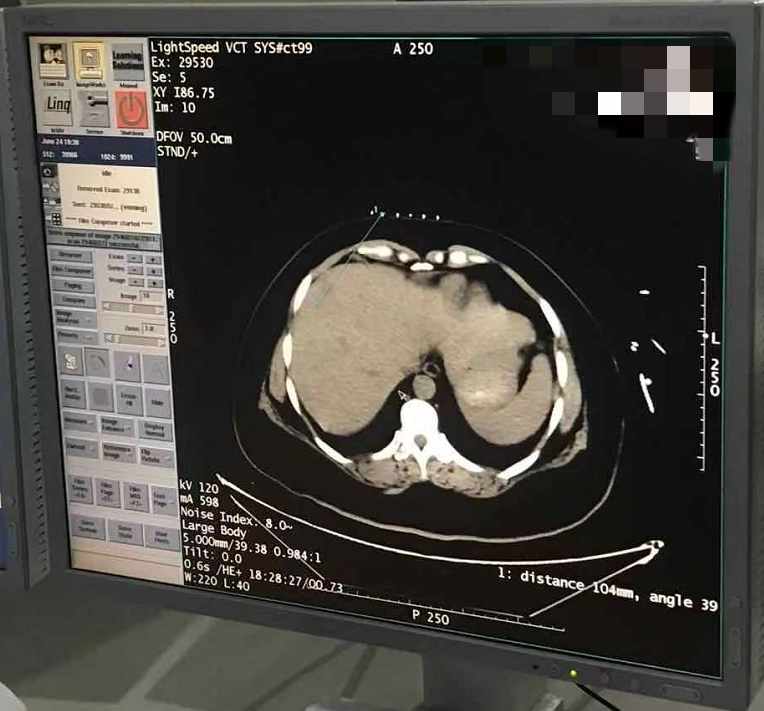

2021年6月份肝部氩氦刀手术

发布人:美国氩氦刀技术官方网站    发布时间:2021/9/22 15:53:00